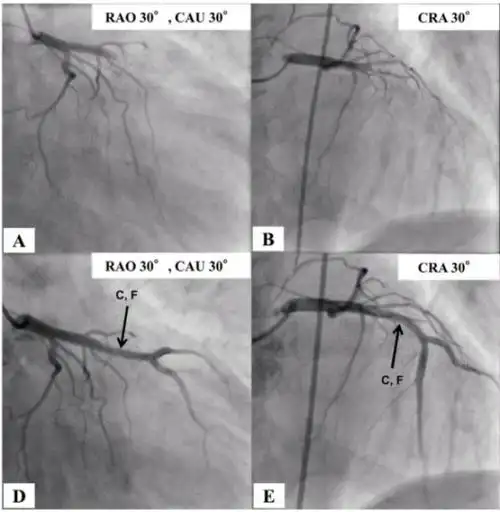

图1 冠脉造影示前降支支架内闭塞及药物球囊扩张术后